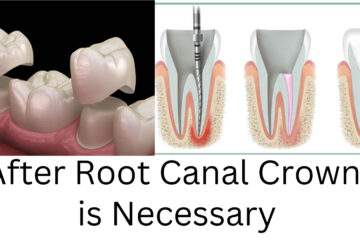

For normal extrinsic tooth stain first Scaling is recommended, then if want more white tooth then bleaching can be an option. Tooth bleaching can give you white tooth. But tooth bleaching is not always indicated; sometimes tooth bleaching can cause other side effects. To remove intrinsic stain or excessive yellow Teeth stains commonly tooth Composite tooth Veneering, Metal Ceramic or Full ceramic Veneering or Crown is indicated. White tooth can gives you bright smile.